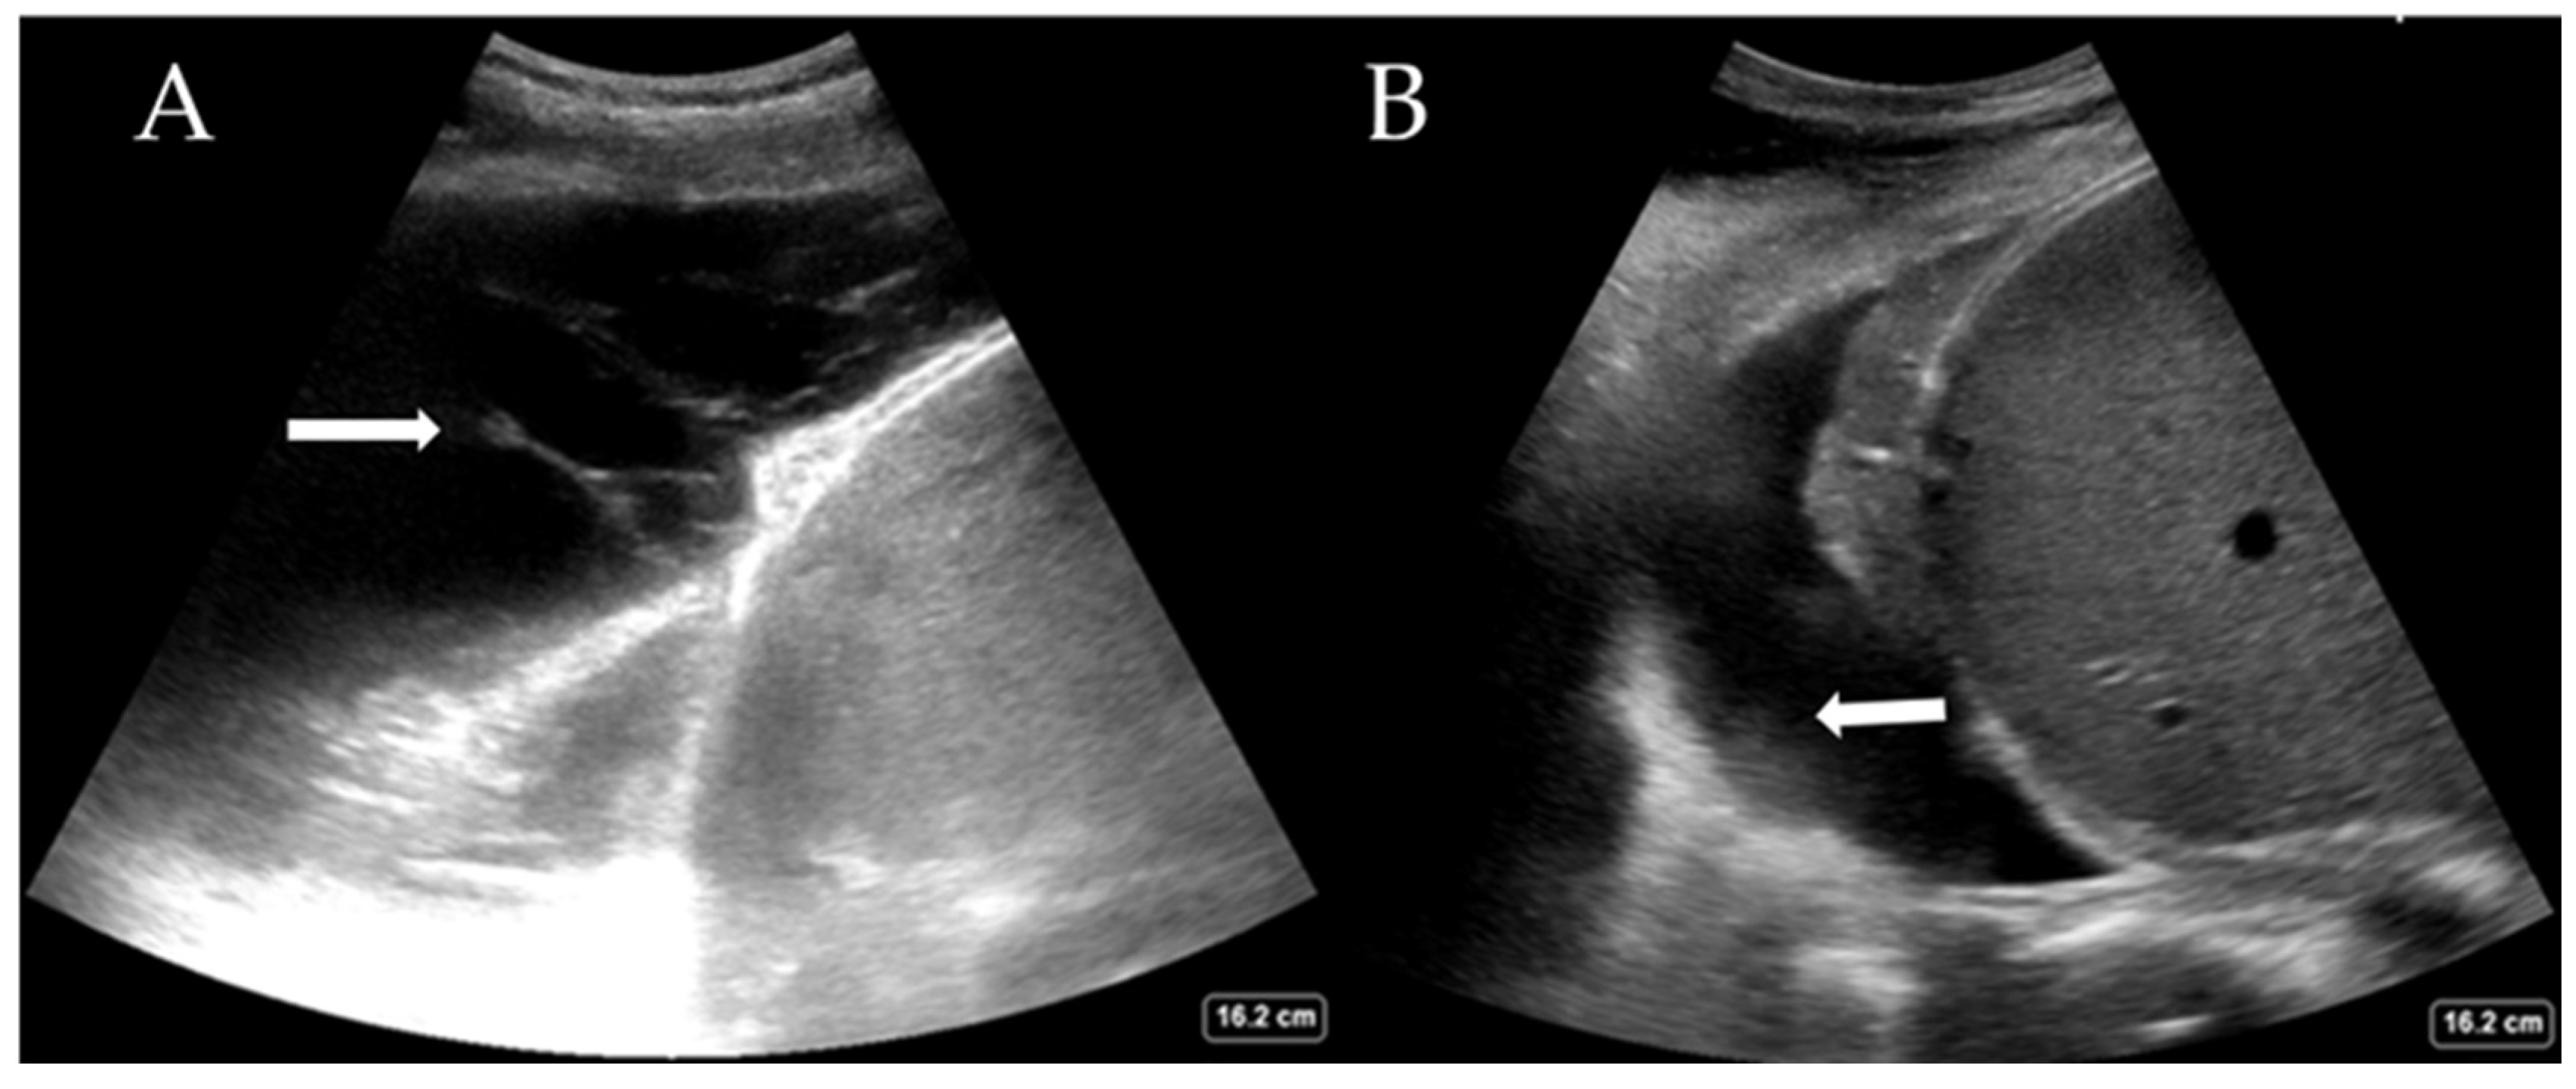

While the definitive differentiation of whether the fluid is likely transudate or exudate requires pleural fluid analysis, LUS can help distinguish between a simple and complex pleural effusion. Complex effusions are associated with the presence of fibrin deposits, septations, or hyperechoic fluid. Complex effusions are often, but not exclusively, exudates. Figure 3A shows a complex effusion with fibrin stranding, likely exudative in nature. This may also guide decision-making regarding drain types (e.g., small or large bore Seldinger vs. surgical) and whether surgical intervention is required. LUS also helps estimate the quantity of pleural effusion present, which is comparable to the volume drained [28,29]. Large effusions often have free-floating lung tissue in them, creating the ‘jellyfish sign’. Other pathological processes, such as haemothorax (Figure 3B) and abscess, can also be elucidated with experience. The British Thoracic Society, UK, now recommends that pleural procedures only be undertaken with LUS guidance [30].

Figure 3.

(A) Complex pleural effusion with fibrin stranding (arrow) and (B) haemothorax with adherent haematoma on the diaphragm (arrow).